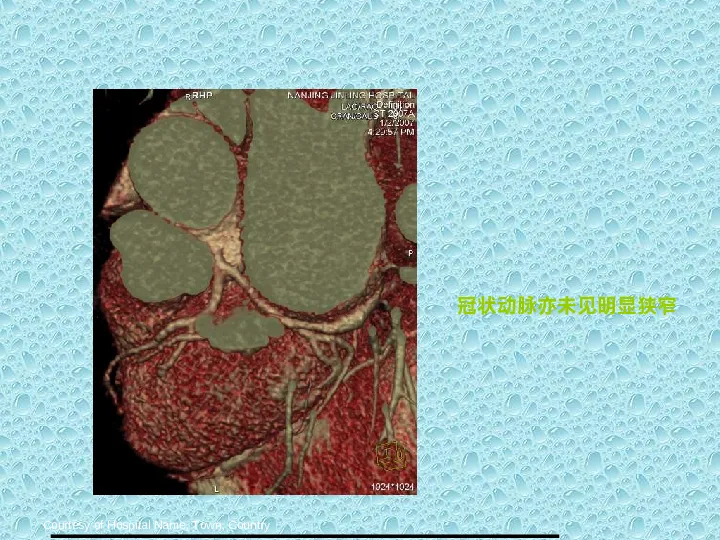

>【影像PPT】双源CT及其临床应用

【影像PPT】双源CT及其临床应用